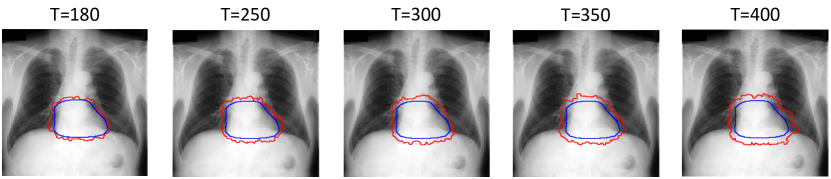

For each of these three datasets, we use three noise settings, denoted by , and . and are two settings synthesized by our Markov process with (expansion) and (shrinkage), respectively. Figure 4 shows examples of our synthesized label noise. We also include the mix of random dilation and erosion noise used by previous work (Zhu et al., 2019; Zhang et al., 2020b; a). This is achieved by randomly dilate or erode a mask with a number of pixels. Note that our Markov label noise can theoretically include this type of noise by setting . Detailed parameters for these settings are provided in the Appendix.

Real-world label noise. To evaluate with real-world label noise is challenging. We are not aware of any public medical image segmentation dataset that has both true labels and noisy labels from human annotators. Therefore, we use a multi-annotator dataset, LIDC-IDRI dataset (Armato III et al., 2015; Armato et al., 2011; Clark et al., 2013), and the coarse segmentation in a vision dataset, Cityscapes (Cordts et al., 2016). The LIDC-IDRI dataset consists of 1018 3D thorax CT scans where four radiologists have annotated multiple lung nodules in each scan. The dataset was annotated by 12 radiologists, and it is not possible to match an annotation to an expert. We use the majority voting as the true labels and the union of four annotations as noisy labels. We process and split the data exactly the same way as Kohl et al. (2018). Cityscapes dataset contains 5000 finely annotated images along with a coarse segmentation by human annotators that we use as the “noisy label”. We only focus on the ‘car’ class because (1) cars are popular objects and are frequently included in images; (2) the coarse annotation of cars is very similar to noisy annotation in medical imaging – they are reasonable distortions of the clean label without changing the topology. See Figure 4(c) for an example. The detailed settings of LIDC-IDRI and Cityscapes can be found in Appendix A.2.1.

Table 1 shows the segmentation results of different methods with synthetic noisy label settings on JSRT , ISIC 2017 and Brats 2020 dataset. Note that QAM cannot be applied to Brats 2020 dataset because their network is designed for 2D only. We compare DICE score (DSC) on testing sets (against the clean labels). For each setting, we train 5 different models, and report the mean DSC and standard deviation. In and , where biases show up in noisy labels, the proposed method outperforms the baselines by a big leap in total case. The compared methods, however, only work when little bias is included, like . is equivalent to setting in our Markov model, resulting in . We also test the proposed method on real-world label noise, results shows in Table 2. Figure 5 shows examples of label correction results. We provide more qualitative results in the Appendix A.4.